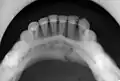

Plain film radiography

Traditionally, plain films of the mandible would be exposed but had lower sensitivity and specificity owing to overlap of structures. Views included AP (for parasymphsis), lateral oblique (body, ramus, angle, coronoid process) and Towne's (condyle) views. Condylar fractures can be especially difficult to identify, depending on the direction of condylar displacement or dislocation so multiple views of it are usually examined with two views at perpendicular angles.[11]

occlusal radiograph of a mandibular parasymphysis fracture